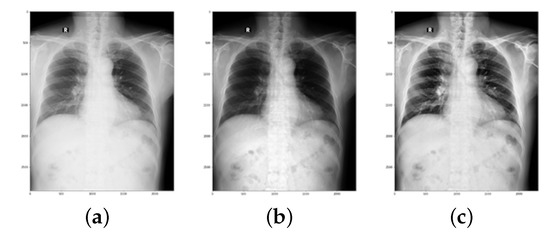

- Image Normalization: Different manufacturers of X-ray devices may provide different-looking X-ray images for the same patient. Overfitting to the device pixel distributions is quite a big problem in computer-aided diagnostic devices; therefore, it is standard practice to apply contrast normalization to minimize this problem. The general idea is to unify the distribution of pixels. This makes X-rays appear a little darker. This procedure generates a view that radiologists would not see in their standard workplace. Using the Reinhard and Macenko approaches, X-ray images were stain-normalized [43,48,49]. A reduction in the color discrepancies of X-ray images improves the classification accuracy of EfficientNet models.